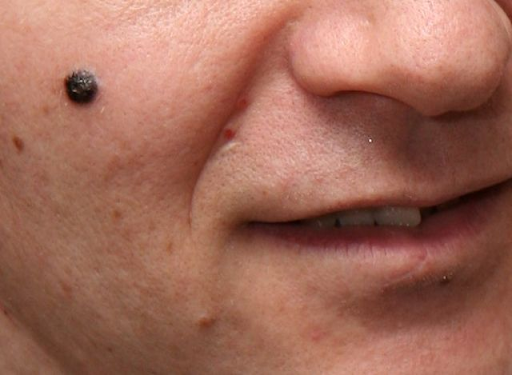

Operare un auto-esame della propria pelle, in particolare delle zone contenenti nevi e lentiggini, è fondamentale per riconoscere tempestivamente la presenza di nei maligni e altri tipi di anomalia, nonché la formazione di nevi acquisiti.

L’auto-esame della superficie cutanea non sostituisce la necessità di controlli dermatologici, ma permette di tenere monitorata efficacemente la presenza e l’aspetto dei nevi tra una visita e l’altra. Per effettuare un auto-esame efficace occorre esaminare l’intera superficie cutanea, includendo anche le zone non accessibili allo sguardo come schiena e cuoio capelluto per mezzo di specchi o aiuto di terzi. Bisogna inoltre controllare scrupolosamente anche il cuoio capelluto e gli interstizi tra le dita di mani e piedi, sotto le unghie e nella zona inguinale e genitale.

I test di controllo della superficie cutanea sono consigliati in modo particolare a chi possiede una quantità elevata di nei sul corpo o ne presenta in posizioni difficili da raggiungere e monitorare autonomamente.

In questo caso è opportuno prenotare e sottoporsi periodicamente alla mappatura dei nei, un tipo di visita dermatologica completamente indolore e non invasiva, all’interno della quale sono acquisite immagini di ogni neo attraverso un’apposita telecamera. Nel corso del tempo il controllo periodico dei nevi permette di valutarne l’evoluzione e intervenire tempestivamente nel caso di formazione di nevi maligni o eventuali melanomi.